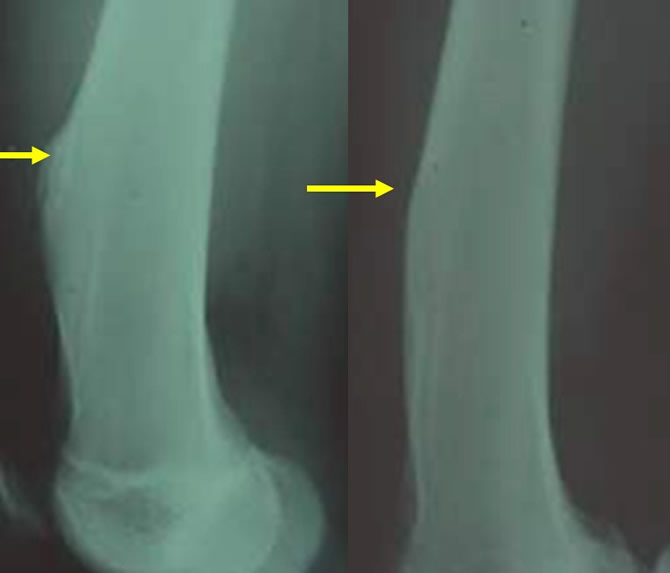

Régression spontanée d'un CD Tibial

Régression spontanée en 9 mois.

Évolution naturelle d'un fibrome non ossifiant

Régression spontanée en 6 mois.

Poussée évolutive menaçant de fracture

Aggravation nette de la plage d'ostéolyse évoluant vers la forme géante du fibrome non ossifiant.